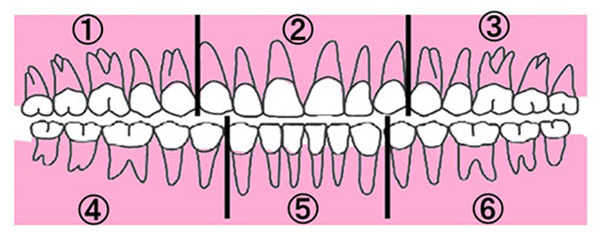

※1ブロックの範囲を図で見る場合はこちらをご覧ください。